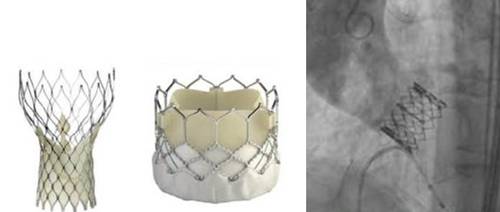

주로 혈관협착을 치료하기 위해 스텐트 삽입 및 풍선 확장술 위주로 시행되던 중재적 시술은 점차 적용 범위를 넓혀 이제는 인공 대동맥 판막을 이식하는 시술도 가능하게 됐다. 관상동맥 스텐트 및 경피적 대동맥 판막 치환술을 받고 건강을 되찾은 이씨가 대표적인 사례다. 경피적이란 말은 피부에 관을 넣어 목표물에 접근한다는 의미다. 피부를 절개하는 외과 수술과 달리 시술 후 큰 흉터가 없는 게 특징이다.

최근 2년간 우리나라에서는 이런 경피적 대동맥 판막 치환술이 17개 병원에서 576명에게 시술됐다. 시술 후 1년 이상 생존한 환자는 91.1%로 치료성적이 좋은 편이다. 중재적 시술의 발전으로 고령이거나 다른 질환이 동반돼 수술의 위험이 큰 경우에도 시술만으로 생명을 구할 수 있게 된 것이다.

![인공 대동맥 판막(좌)을 이용한 경피적 대동맥 판막 삽입술(우) [강남세브란스병원 제공=연합뉴스]](https://img1.daumcdn.net/thumb/R658x0.q70/?fname=https://t1.daumcdn.net/news/201807/18/yonhap/20180718070021999dluh.jpg)